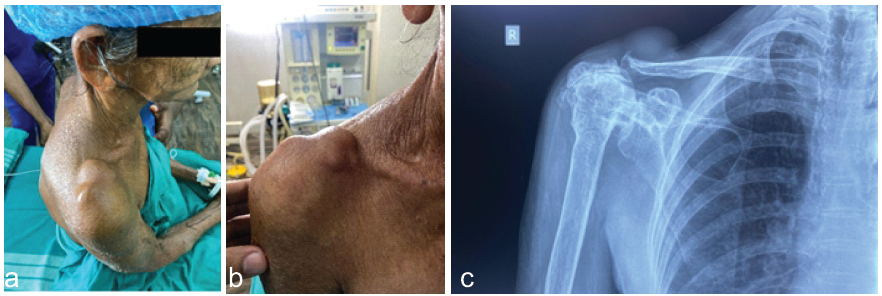

On examination, a soft and mobile lump was noted around the right AC joint, measuring approximately 8 × 5 cm, suggesting the potential presence of a ganglion cyst (Fig. 1a and b). The skin in that area looked normal, and there were no indications of neurovascular problems in the right arm. The active range of motion for the right shoulder was significantly restricted.

Figure 1: (a, b, c) Pre-operative.

X-ray showed degenerative changes in the AC and glenohumeral joint. Deformed and decreased Humer acromial interval (Fig. 1c).